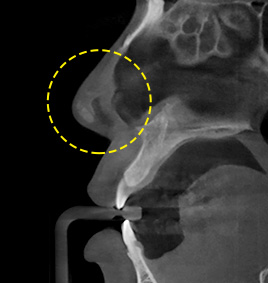

CASE 3When silicone and nasal septa are bent

The bent nasal bone and nasal septa are adjusted, and silicone is inserted.